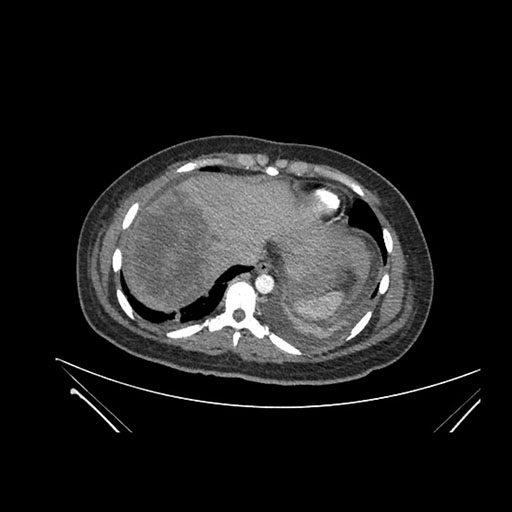

Imaging Analysis

Look through the patient's CT scan to identify any areas of concern for the necessary procedure.

Axial Arterial

Based on initial findings, which issue(s) would you be most concerned about?